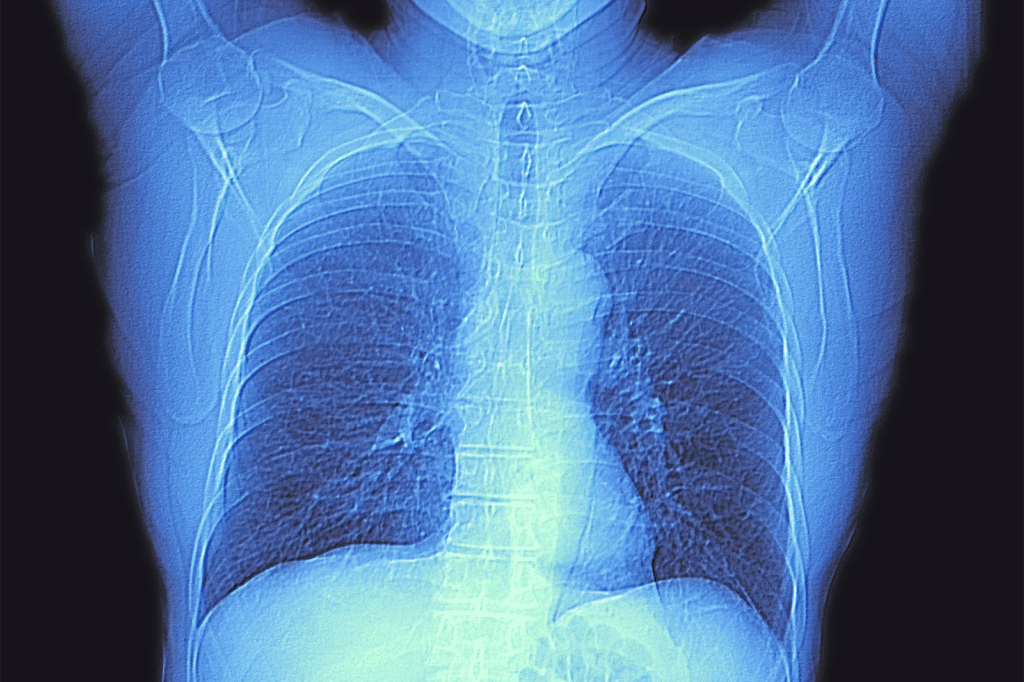

Comparison Between CT Scans and Traditional Chest X-rays

CT scans give a 3D view of the chest, unlike X-rays’ 2D view. This is especially helpful for complex cases or when a precise diagnosis is needed. CT scans can tell different soft tissues apart, showing more about organs and vessels.

Following Abnormal Chest X-ray Results

Abnormal chest X-rays lead to chest CT scans. These scans give clearer images of the chest. They help us understand what’s wrong.

How does a chest CT scan differ from a traditional chest X-ray?

A chest CT scan gives clearer images than a chest X-ray. It’s better for spotting problems in the lungs, heart, and nearby areas.